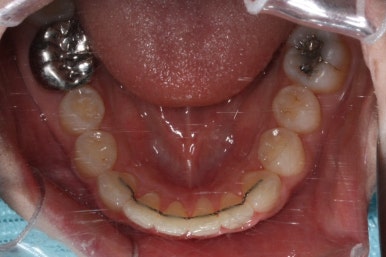

유지장치를 하지 않은 상태였기 때문에 원래대로 앞니가 되돌아간 것을 볼 수 있습니다.

이번에는 약간 다른 양상으로 조절을 하기 위해서 MTA 장치 말고 일반 브라켓을 붙이기로 하였습니다.

이번에 사용한 장치는 클리피씨라고 하는 세라믹 자가결찰 장치였습니다.